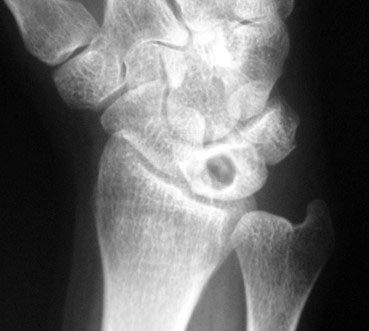

Figura 4: semilunar con esclerosis radiológica y pérdida de altura. Cúbito minus

Junto con los síntomas y la exploración física, es necesario realizar pruebas de imagen radiológicas. En la radiografía simple se pueden observar cambios en la densidad ósea del semilunar y las variantes morfológicas óseas (figura 4).

II: esclerosis radiológica con morfología normal (figura 6).

Figura 6 estadio II de la enfermedad de Kienböck